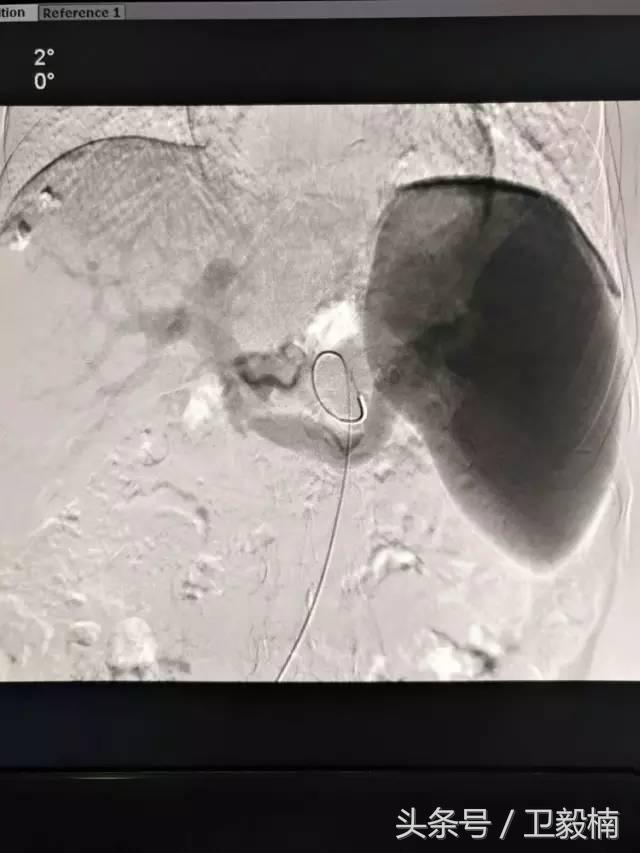

2、经导管血管栓塞法(Transcatheter embolization)

经原血管造影的导管或特制的导管,将栓塞物送至靶血管内,一是治疗内出血如外伤性脏器出血、溃疡病、肿瘤或原因未明的脏器出血。另一是用栓塞法治疗肿瘤,因肿瘤循环部分或全部被栓塞物阻断,以达控制肿瘤之生长,或作为手术切除的一种治疗手段;亦可用于非手术脏器切除,例如注射栓塞物质于脾动脉分支内,即部分性脾栓塞,以治疗脾功亢进,同时不影响脾脏的免疫功能。

常用的栓塞物质如自体血凝块、明胶海绵、无水酒精、聚乙烯醇、液体硅酮、不锈钢圈、金属或塑料小球及中药白芨等。